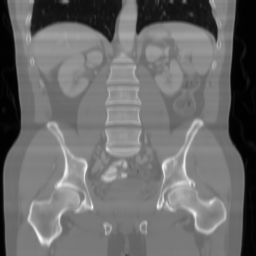

| Ground Truth | Input | DDS-100 [chungdecomposed] | DDS-200 [chungdecomposed] | NERD-P (Ours) |

| PSNR = dB | PSNR = 14.56 dB | PSNR = 37.42 dB | PSNR = 37.81 dB | PSNR = 39.15 dB |

![]() |

| PSNR = dB | PSNR = 15.58 dB | PSNR = 34.28 dB | PSNR = 34.67 dB | PSNR = 35.83 dB |

| PSNR = dB | PSNR = 12.43 dB | PSNR = 36.20 dB | PSNR = 36.56 dB | PSNR = 37.23 dB |

Main results: In Table 1, we present quantitative results and in Figure 2, we show visualizations in the axial, coronal, and sagittal planes. Our methods consistently outperform the second-best baseline across most views, achieving nearly 1 dB higher PSNR on average. Despite incorporating a few additional input updates to enforce data consistency, our method reaches competitive performance with only 30 sampling steps. Based on the visualizations, we observe that DDS introduces slight artifacts along the horizontal direction, particularly noticeable in the coronal and sagittal views. In contrast, our method produces cleaner reconstructions with fewer artifacts in these orientations.